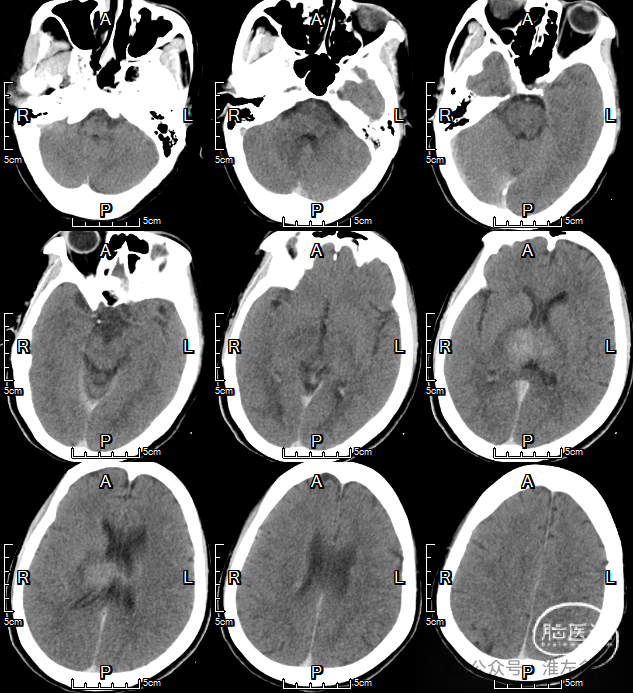

CT平扫:双侧丘脑低密度肿胀,直窦-大脑大静脉血栓高密度。

CTV:左侧横窦-乙状窦细小,右侧横窦充盈缺损,深部静脉系统未见显影,上矢状窦显影不清晰。

CT平扫:双侧丘脑静脉梗死区域造影剂染色。

CT平扫:右侧丘脑静脉梗死区稍高密度。

CT平扫:双侧丘脑病变范围明显改善。

CT平扫:仅见右侧丘脑和内囊少许低密度影。